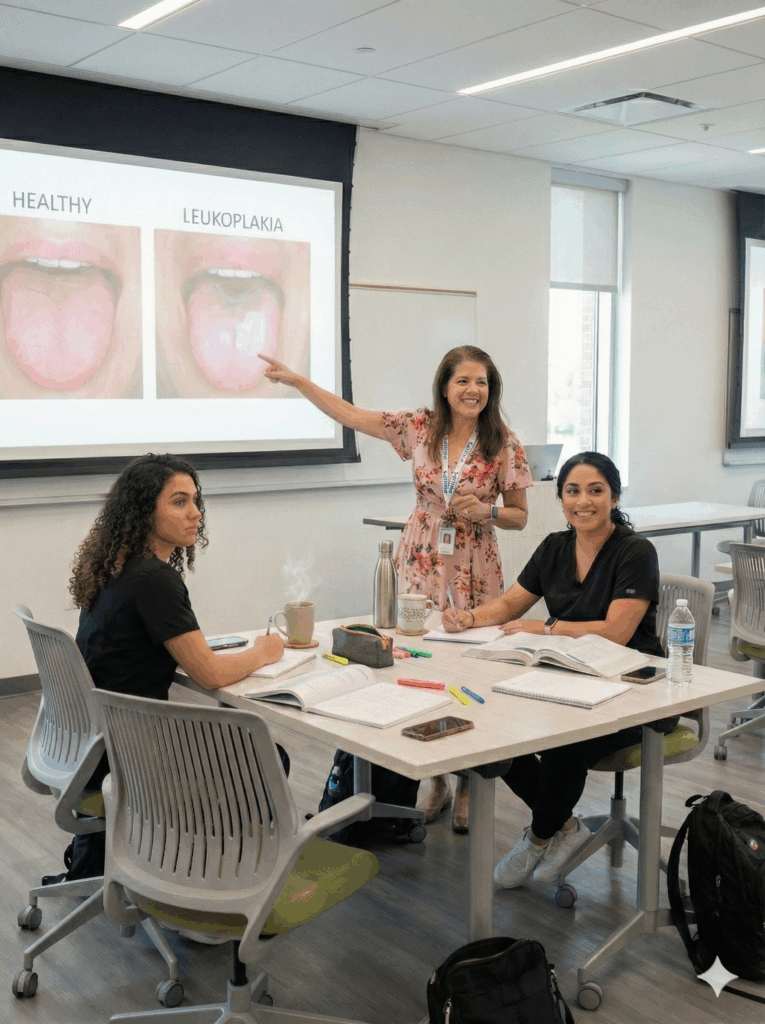

Practice, explore, and strengthen your diagnostic eye

Interactive Oral Pathology Workshops

Designed for dental professionals who learn best through visual exploration and guided clinical reasoning. These workshops dive into real cases, diagnostic patterns, and the subtle features that distinguish one lesion from another, building confidence in the operatory and sharpening your diagnostic eye with every session.